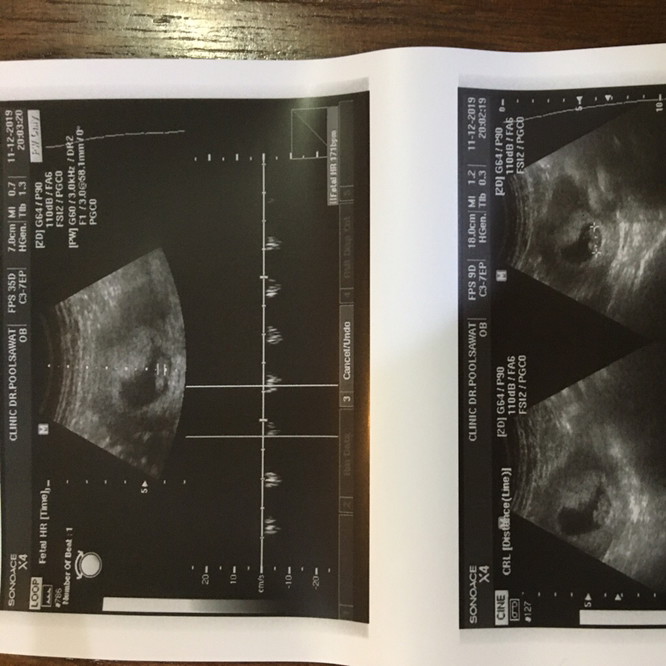

9.2สัปดาห์ค่ะ